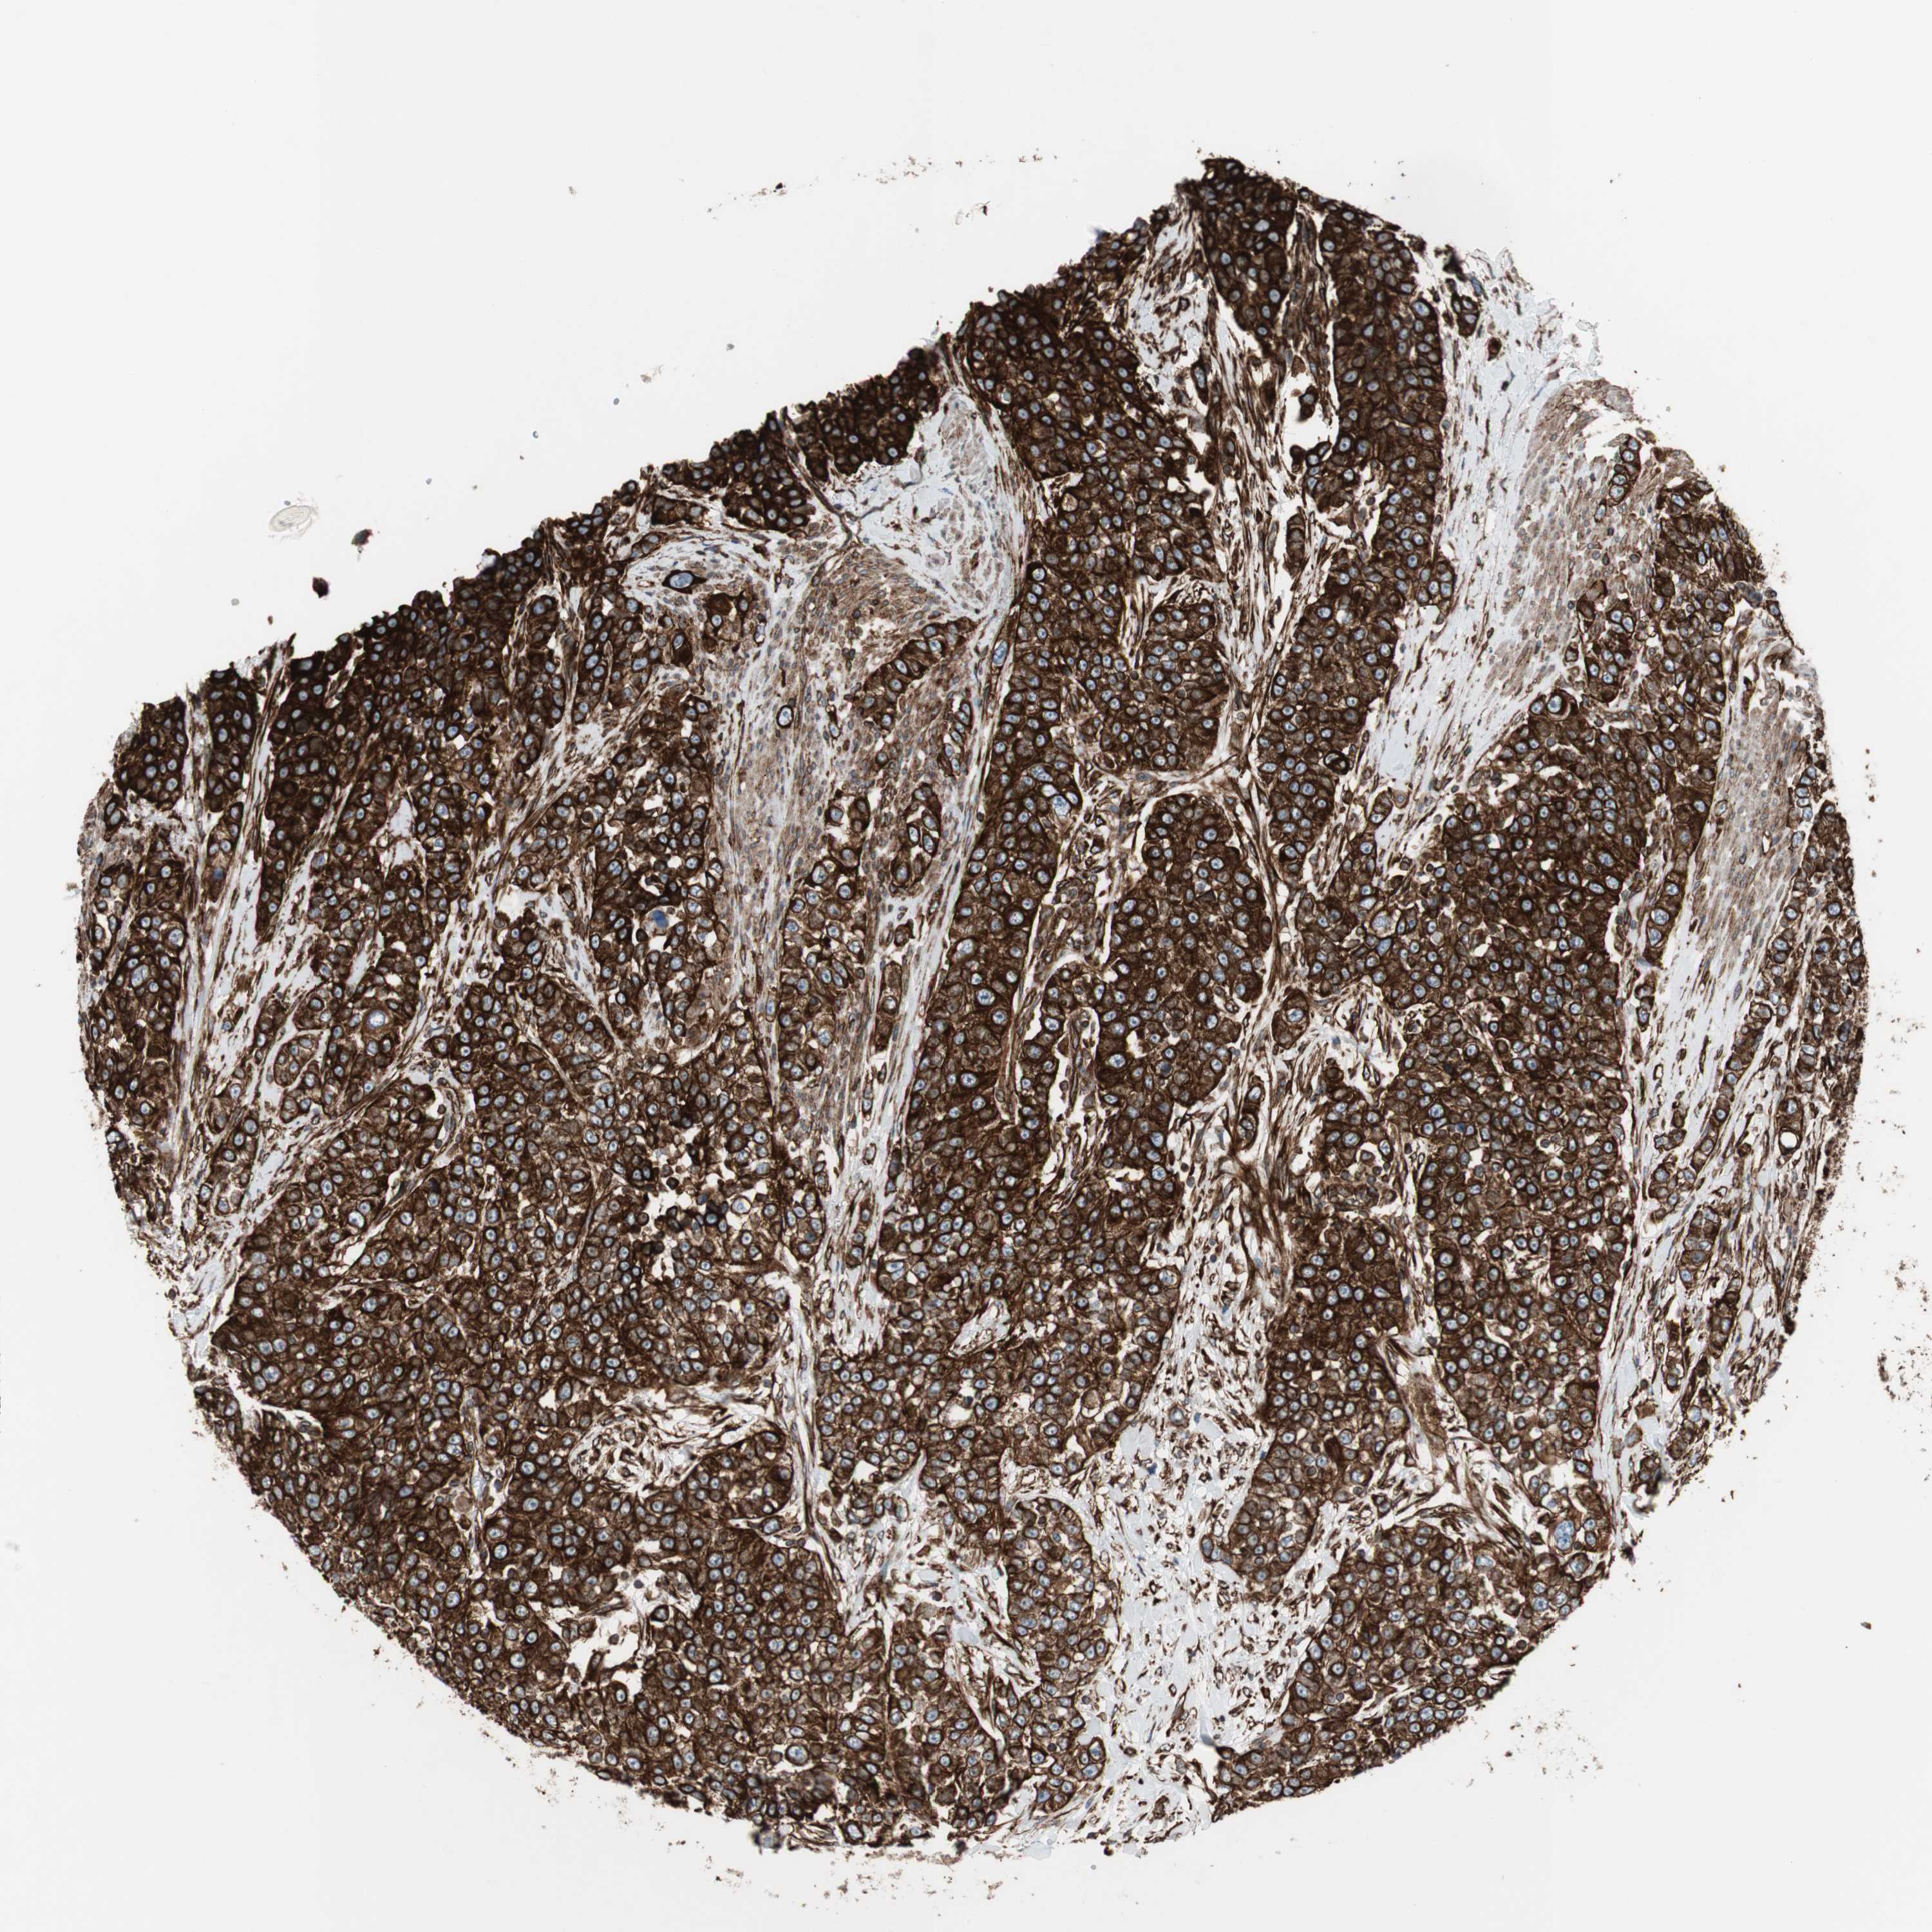

UROTHELIAL CANCER - Protein expressioni

A mouse-over function shows sample information and annotation data. Click on an image to view it in a full screen mode. Samples can be filtered based on level of antibody staining by selecting one or several of the following categories: high, medium, low and not detected. The assay and annotation is described here.

Antibody stainingi

Antibody staining in the annotated cell types in the current human tissue is reported as not detected, low, medium, or high, based on conventional immunohistochemistry profiling in selected tissues. This score is based on the combination of the staining intensity and fraction of stained cells.

Each image is clickable and will lead to virtual microscopy that enables deeper exploration of all samples and also displays staining intensity scores, fraction scores and subcellular localization as well as patient and tissue information for each sample.

Antibody HPA007342

Staining

High

Medium

Low

Not detected

Intensity

Strong

Moderate

Weak

Negative

Quantity

>75%

75%-25%

<25%

None

Location

Nuclear

Cytoplasmic/membranous

Cytoplasmic/membranous,nuclear

Urothelial carcinoma, High grade